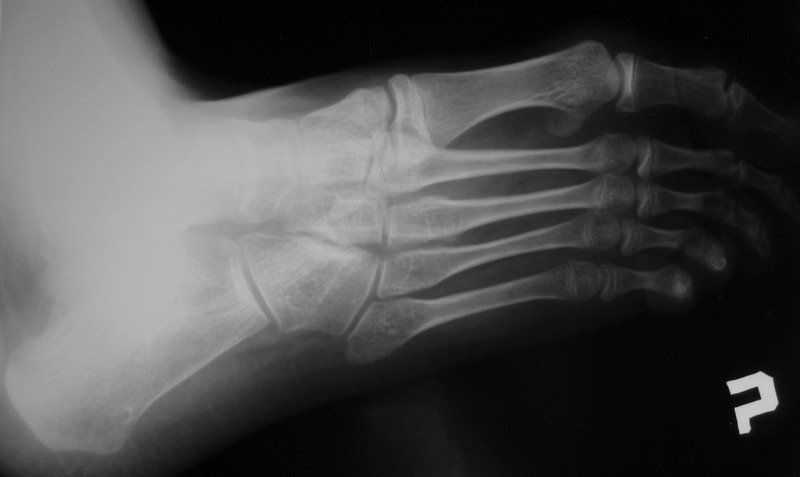

Пациент 15 л., болезнь Литтля, спастический нижний парапарез, интеллект высокий. Ребенок настроен на активный образ жизни. С недавнего времени начал ходить без дополнительной опоры. Появилась проблема с левой стопой - во время ходьбы опора приходится на смещенную кнутри таранную кость.

Может образоваться болезненный натоптыш или язва. Общепринятой операцией является трехсуставной артроде с мобилизацией таранной кости. Выполнять такую операцию у спастика и в раннем возрасте проблематично. Родстьвенники тем более готовы материально и морально осуществить хирургическое лечение за рубежом, если оно показано и возможно. Предпочтительно в Австрии и Германии. Если кто-то посоветует координаты таких клиник - были бы признательны.